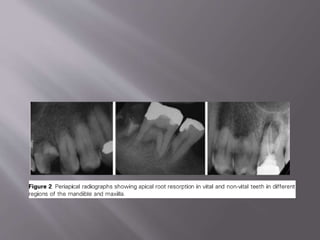

Radiographic findings

Progressive cavitations involving root and adjacent alveolar bone.

Result in total loss of tooth structure within a few months.